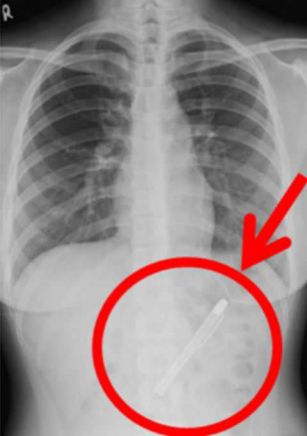

Заподозрив серьезную патологию, специалисты направили больную на рентгенографию, объяснив ей, что это исследование поможет им установить причину недомогания, и, как следствие, поставить правильный диагноз и назначить лечение. Однако, как выяснилось позже, они сильно ошибались в своих прогнозах - вместо признаков заболевания желудка медики увидели инородный предмет.

А после более внимательного изучения снимков с изумлением поняли, что странный объект не что иное, как авторучка.

После определения причины длительных болей девушка была в срочном порядке доставлена в операционную. К счастью, хирургам удалось извлечь 10-сантиметровую письменную принадлежность и не травмировать при этом ткани и сосуды.